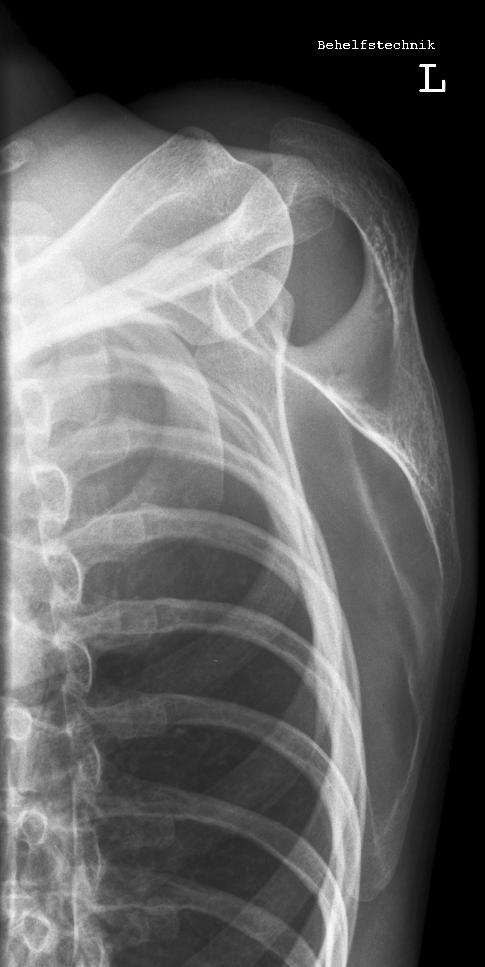

Schulter a.p.

22_2.jpg

Fehler

Hier erfolgte eine ungenügende Rotation in der Schulter, so dass das Gelenk nicht frei dargestellt wurde.

Abhilfe

Abhilfe bringt eine weitere Drehung des Patienten nach dorsal.